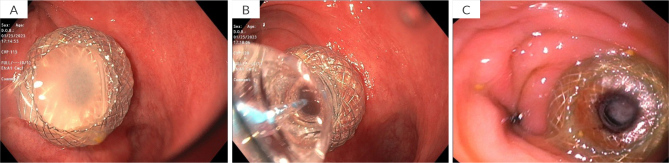

结直肠黏液囊肿是一种罕见的发生在胃肠道的黏液囊肿,对诊断和治疗提出了挑战。我们报告了首例使用腔内金属支架(LAMS)成功治疗腔外结直肠黏液囊肿的病例。65岁男性,既往有憩室炎病史,行部分结肠切除术后出现便秘和腰痛。计算机断层扫描(CT)显示直肠吻合口附近有一个5.4厘米的囊性结构。超声内镜(EUS)发现上皮下病变呈“洋葱皮”状,吸痰细胞学证实为结肠-结肠粘液囊肿。处理包括eus引导放置8 × 8 mm LAMS,允许引流,冲洗和吸痰腔。在2年的随访期间,完全解决,无复发。本病例证明了先进的内镜技术,特别是LAMS在治疗腔外结直肠粘液囊肿方面的潜力。虽然需要进一步的研究来比较LAMS与其他治疗方式的疗效,但该程序为某些患者提供了手术的微创替代方案。学习要点:一种治疗罕见的结肠黏液囊肿的新方法,使用顺腔金属支架。

Colorectal mucoceles are rare mucinous cysts arising in the gastrointestinal tract and presenting diagnostic and therapeutic challenges. We report the first successful treatment of an extraluminal colorectal mucocele using a lumen-apposing metal stent (LAMS). A 65-year-old male with a known medical history of diverticulitis treated with a partial colectomy presented with constipation and low back pain. Computed tomography scan (CT) revealed a 5.4 cm cystic structure adjacent to the rectal anastomosis. Endoscopic ultrasound (EUS) found a subepithelial lesion with an "onion peel" appearance, and aspiration cytology confirmed a colo-colonic mucocele. Management consisted of EUS-guided placement of an 8 × 8 mm LAMS, allowing for drainage, irrigation, and suctioning of the cavity. Complete resolution was achieved without recurrence over a 2-year follow-up period. This case demonstrates the potential of advanced endoscopic techniques, particularly LAMS, in managing extraluminal colorectal mucoceles. While further research is needed to compare the efficacy of LAMS with other treatment modalities, this procedure offers a minimally invasive alternative to surgery for certain patients.

Learning points: Novel approach to treat a rare case of colorectal mucocele using a lumen-apposing metal stent.